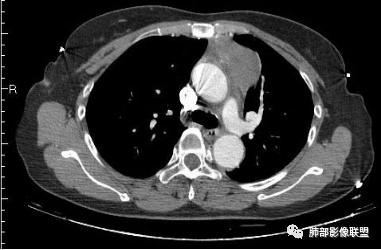

2.胸膜掀起,右侧内乳动脉略增粗,定位右前上纵隔内占位。

3.右上纵隔囊实性占位,边界清楚。中央见点状脂肪密度影,边缘见一点状钙化影,增强不均匀环形强化。

4.四天内病灶变化快,块影增大且不规则,包膜似不完整,边界不清,上份可见浸润或渗出,与周围心脏大血管及心包等间隙不清。胸水增多。

5.未见明显淋巴结增大

第一次的检查符合胸腺瘤影像学改变,短期内的形态学改变及突然出现的边界模糊或浸润等,符合出血或炎症。